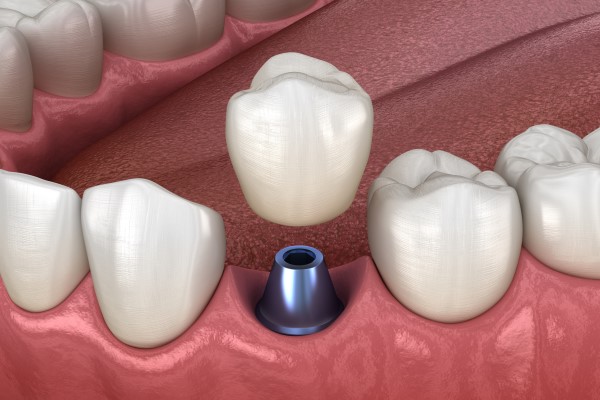

Understanding Dental Implants: A Comprehensive Guide

Dental implants have revolutionized the field of restorative dentistry, providing a durable and aesthetically pleasing solution for tooth loss. These titanium posts are surgically placed in the jawbone to serve as artificial roots for replacement teeth. In this article, we will explore various types of dental implants and related dental services, including single implants, immediate implants, implant-supported bridges, sinus lift procedures, and more.

Single Implants

A single implant is the ideal solution for replacing a single missing tooth. The procedure involves placing a titanium implant into the jawbone, allowing it to fuse with the bone in a process called osseointegration. Once healed, a custom-made crown is attached to the implant, restoring both function and aesthetics. Single implants are known for their durability and ability to preserve surrounding bone and teeth, making them a valuable dental services for patients in need of tooth replacement.